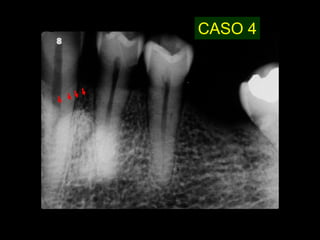

CASO 4

• 29.